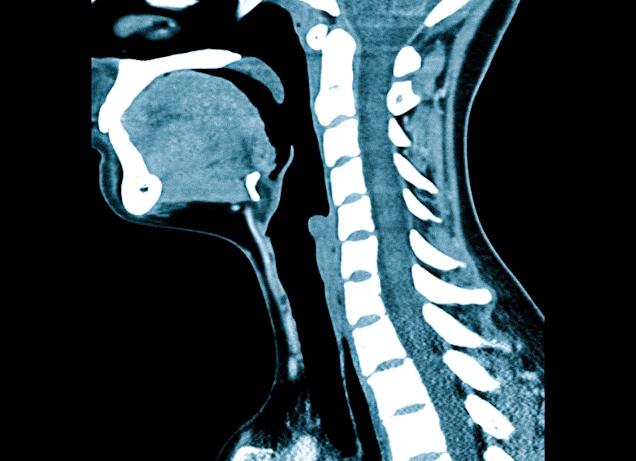

КТ (компьютерная томография) органов шеи и гортани с контрастом

Компьютерное сканирование шеи и головы, гортани назначается ЛОР-врачом, гастроэнтерологом, онкологом. Исследование показывает строение позвонков, состояние сосудов, соседних органов.

По качеству томография значительно превосходит рентгенографию, хотя в основе лежит рентгеновское излучение. Изготовление серии срезов исследуемой области через несколько миллиметров, программное создание пространственной модели – особенности увеличивают чувствительность, специфичность исследования.

Нативная компьютерная томография щитовидной железы и шеи показывает костные структуры, увеличенные лимфатические узлы, выявляет новообразования.

Контрастирование (КТ с контрастом) позволяет отслеживать сосуды, изучать контуры анатомических образований, верифицировать опухоли, растущие внутрь и наружу стенки (эндо, экзофитный рост).

КТ шеи – сканирование мягких тканей и органов шеи с помощью рентгеновского излучения с получением послойных снимков высокого разрешения. Зона исследования охватывает слюнные железы, гортань, трахею, пищевод, щитовидную и паращитовидные железы, лимфатические узлы, мышцы и подкожно-жировую клетчатку шеи. С помощью компьютерной томографии шеи могут быть диагностированы внеорганные патологические процессы (опухоли, кисты, абсцессы, флегмоны), эндокринная патология, травмы и инородные тела, первичное опухолевое и метастатическое поражение данной области. Исследование производится в аксиальной, коронарной и сагиттальной проекциях; может включать использование контраста или быть нативным.

КТ шеи применяется в диагностических целях менее полувека. Методика основана на использовании рентгеновского излучения, при этом в отличие от обычной рентгенографии сканирование проводится при вращении рентгеновской трубки, а данные фиксируются множеством датчиков, что обеспечивает небольшую продолжительность и высокую информативность исследования. КТ шеи применяется в области онкологии, оториноларингологии, травматологии, реже назначается гастроэнтерологами и другими специалистами. Процедура не входит в список рутинных методов обследования и выполняется после первичной рентгенографической и УЗ-диагностики.

КТ шеи осуществляется для выявления обширного списка патологий, как и МРТ данной области. Оба метода обладают высокой информативностью и являются неинвазивными. Для увеличения информативности КТ шеи в большинстве случаев проводится с применением контрастного вещества. Методика позволяет визуализировать мягкие ткани, сосуды и стенки полых органов, преимущественно используется в диагностике патологий мягких тканей и в сфере онкологии – как с целью первичного поиска опухолей, так и для получения дополнительной информации в ходе предоперационной подготовки. КТ шеи менее информативна в отношении сосудов, в то время как МРТ позволяет подробно изучить внутреннее строение интимы артерий, что важно при выявлении начальной стадии сосудистых патологий. Особенности МР-обследования делают его предпочтительным в диагностике патологий хрящей гортани. Кроме того, МРТ часто выполняется нативно.